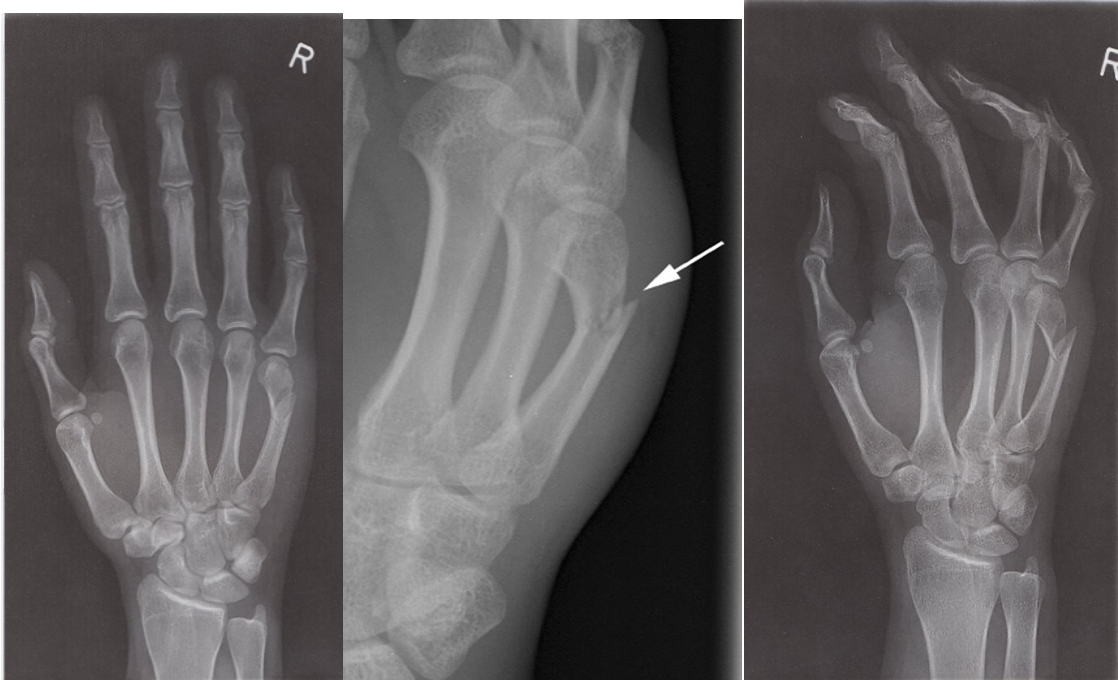

A fracture of the 4th or 5th metacarpal neck is called a boxer’s fracture because it is usually caused by a closed fist forcibly coming into contact with a solid surface

Fracture of the fifth metacarpal - X-ray right hand (PA view) & Fracture of the fifth metacarpal -X-ray right hand (oblique view) An acute oblique fracture of the fifth metacarpal neck.